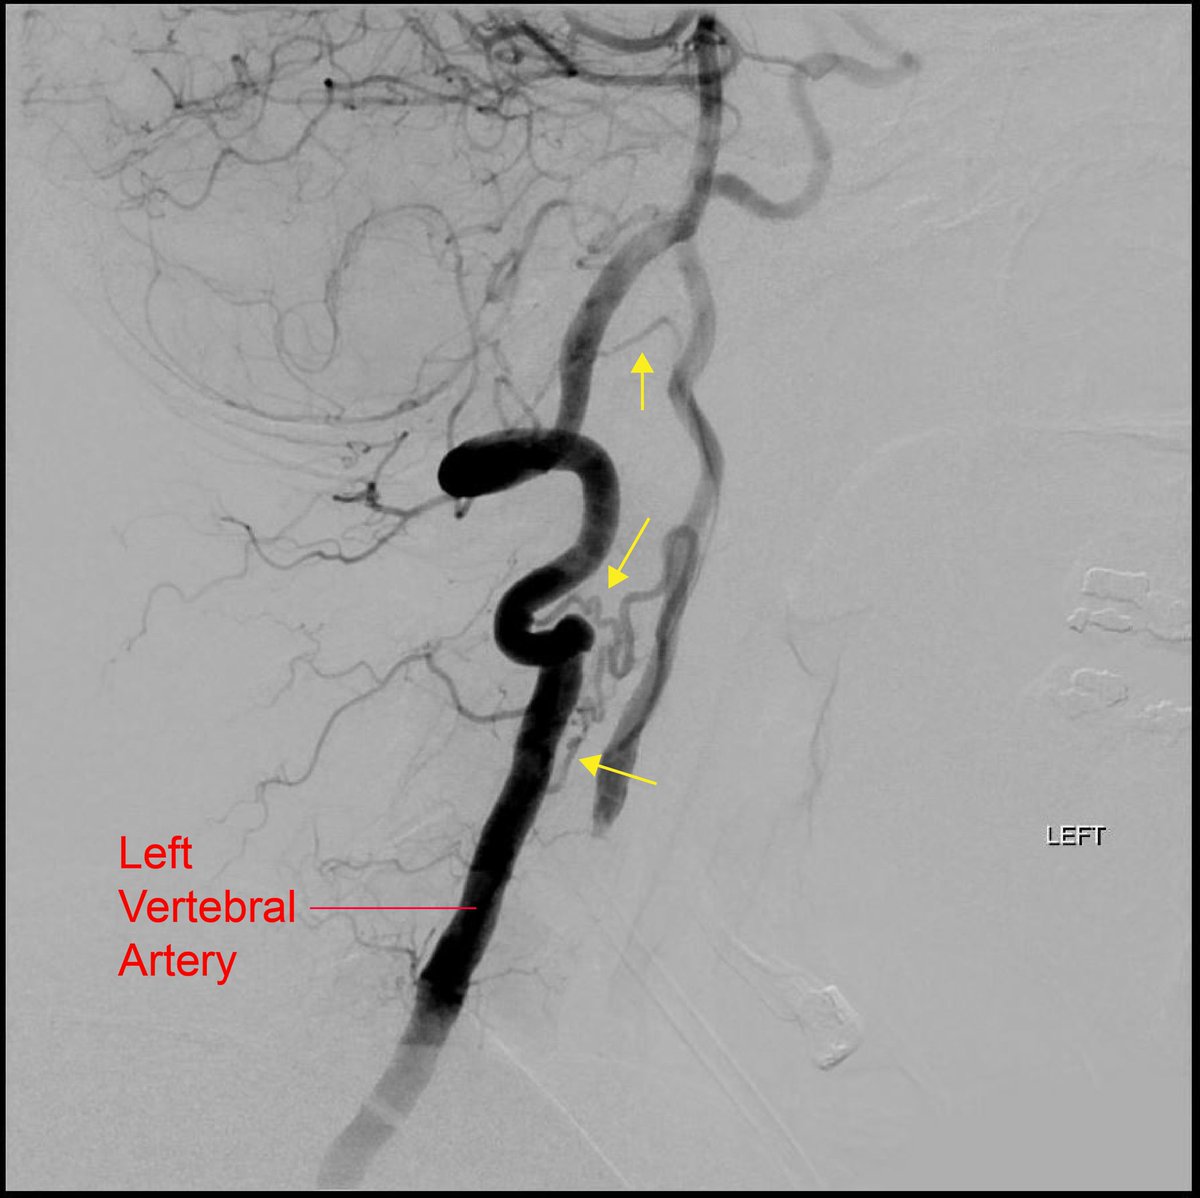

@YNIScommittee @andrewyu8 @RaghavMattay @DoctorSiz @DrJessicaCampos Agree that this is left cervical ICA occlusion with collateralization from the left vertebral artery segmental branches, which appear to be musculospinal collaterals feeding back into the ICA

This is a left vertebral artery angiogram in a middle aged patient presenting with transient aphasia. Can you guess what is going on here? What are the vessels marked by yellow arrows? @andrewyu8 @CharlesBeaman @RaghavMattay @DoctorSiz @DrJessicaCampos